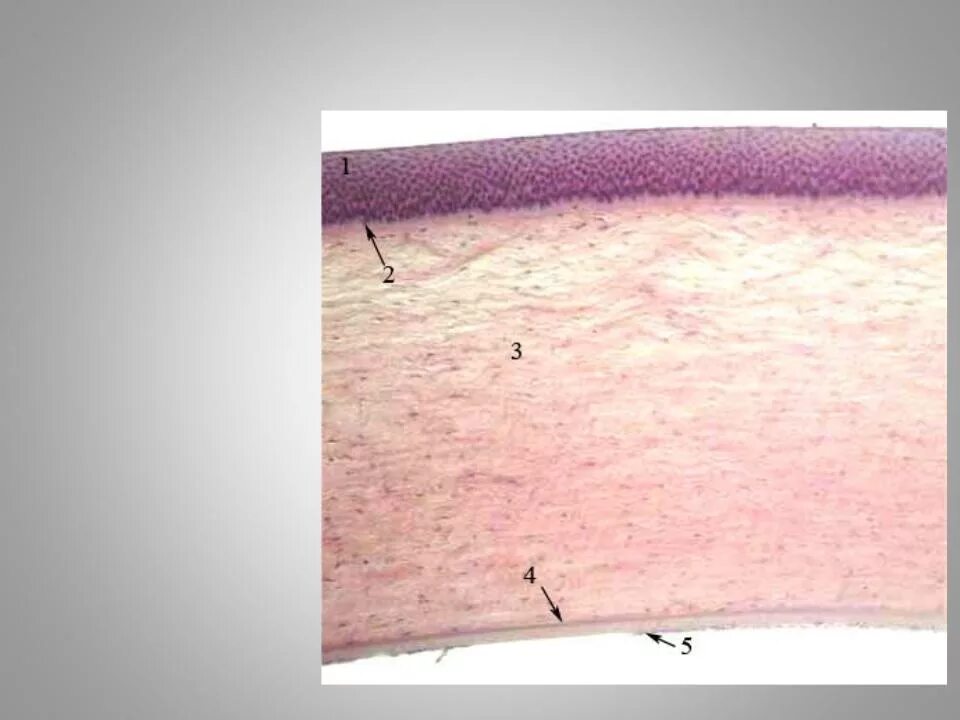

Роговица глаза гистология препарат